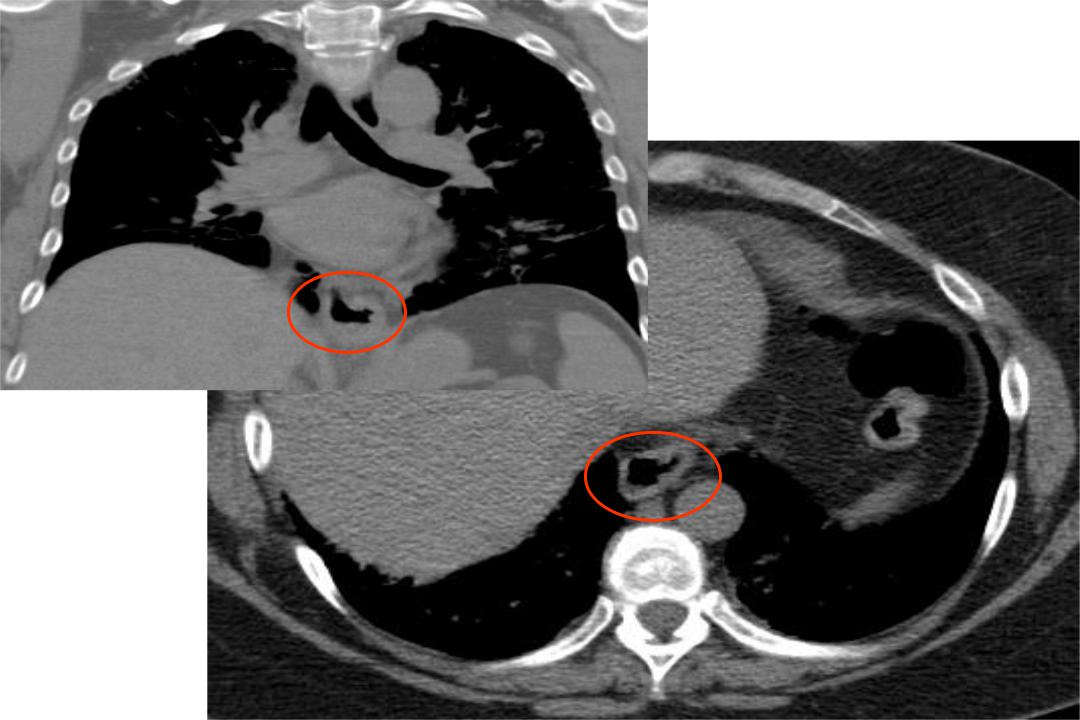

A. Коронарный срез: утолщение слизистой желудка на уровнем диафрагмы

B. Аксиальный срез